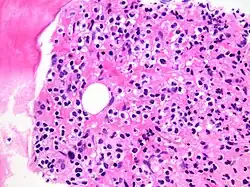

Immune Infiltration

This occurs when immune cells like lymphocytes and macrophages migrate into tissues in response to infection, injury, or inflammation, aiding in defense and healing but potentially contributing to autoimmune diseases if misdirected.[1] Immune cells (especially lymphocytes) also infiltrate into malignant tumors and other neoplasms.[2]